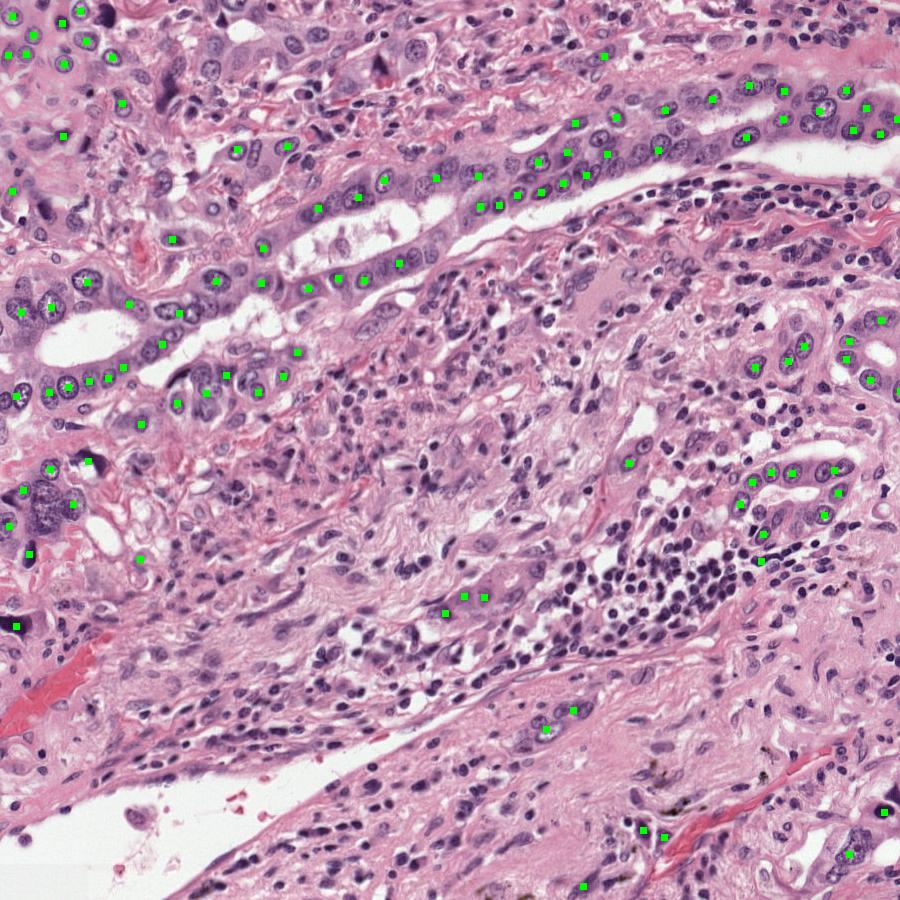

Figure 9: Visual comparison of ground truth and UAM predictions. Tumor cells are highlighted in green.

Refer to caption

(a) Ground Truth1

(b) Prediction1

(c) Ground Truth2

(d) Prediction2

Figure 10: Visual comparison of ground truth and UAM predictions. Tumor cells are highlighted in green.

We provide a visualization of the Ground Truth, BiomedParse-generated, and UAM-generated masks in Figure 7. The multimodal UAM model demonstrates the capability to provide a more accurate mask, which we attribute to its effectiveness in leveraging the cell radiomics information from each image. This finding underscores the significant advantage and effectiveness of the multimodal UAM architecture. More visualization results are shown in Figures 891011, indicating the effectiveness of UAM that highlights tumor cells on H&E slides based on radiomics data, facilitating pathologist interpretation.